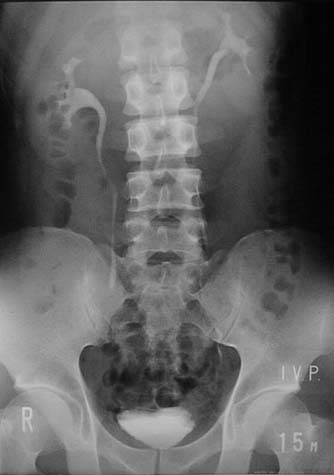

15分後の写真

主に腎盂、腎杯、上部尿管の形態を見ます。

膀胱も見えてきています。